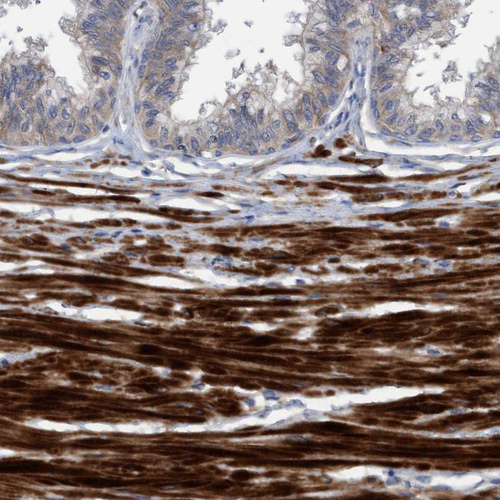

Immunohistochemistry analysis in human placenta and lymph node tissues using HPA020587 antibody. Corresponding GULP1 RNA-seq data are presented for the same tissues.